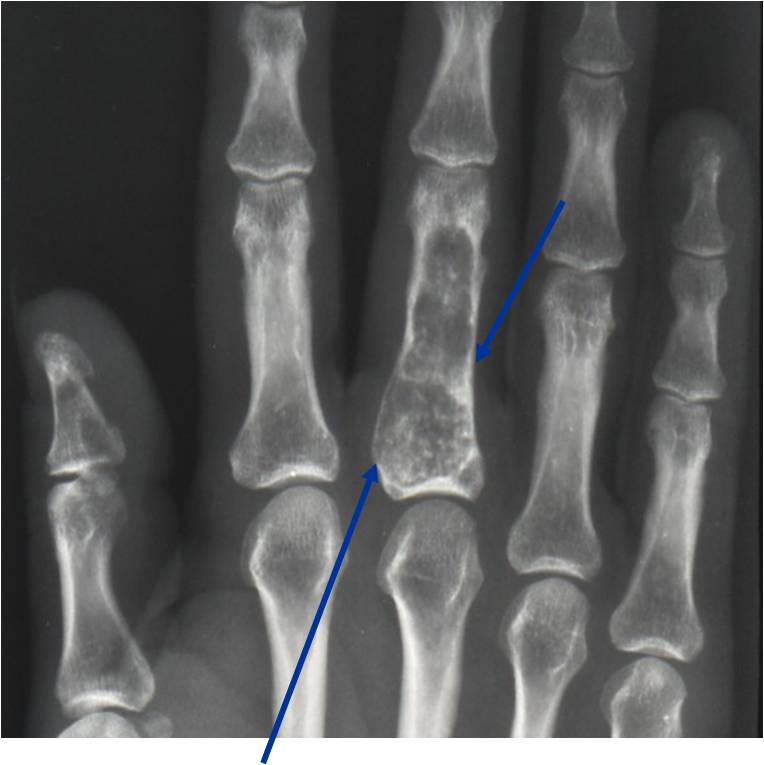

- Localized, radiolucent defect usually with punctate calcifications

- Calcifications are typical but not always present

- Matrix may demonstrate various degrees of calcification

- Calcifications are stippled, punctate, popcorn like calcifications and “Ring and Arc” calcifications

- Cartilage tumors grow in a lobular manner. The perimeters of the lobules undergo

- enchondral ossification that may calcify. If the entire perimeter of the lobule calcifies it appears

- radiographically as a “Ring”. If a portion of the perimeter of a lobule calcifies it forms an “Arc” on

- an X-ray.

- Cortex may be scalloped and thinned in the phalanges

Plain X-Ray:

- Geographic lytic lesion

- Central often metaphyseal in long bones

- Expansile remodeling with thinned cortex

- Chondroid matrix with calcifications in majority of tumors

Geographic Lesion Bony Expansion Minimal Calcification Some Enchondromas do not calcify

Geographic lesion Stippled calcifications in lesion Phalanx is expanded Significant endosteal scalloping No cortical destruction No soft tissue extension Cortex Scalloped and Expanded